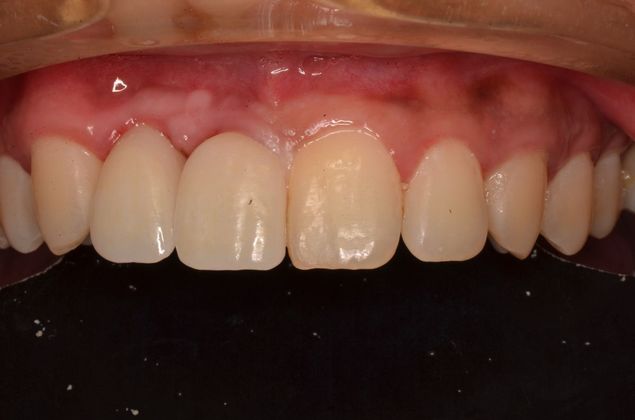

Two implants with crowns replacing infected root canals and old porcelain fused to metal crowns